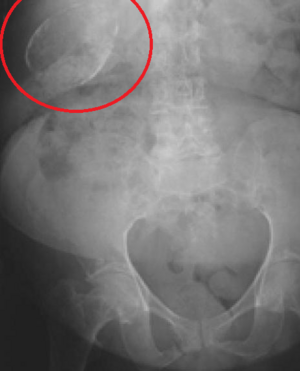

Porcelain Gallbladder

Porcelain gallbladder on X-ray

Porcelain gallbladder is a calcification of the gallbladder believed to be brought on by excessive gallstones, although the exact cause is not clear. As with gallstone disease in general, this condition occurs predominantly in overweight female patients of middle age. It is a morphological variant of chronic cholecystitis. Inflammatory scarring of the wall, combined with dystrophic calcification within the wall transforms the gallbladder into a porcelain-like vessel. Removal of the gallbladder (cholecystectomy) is the recommended treatment.

Abdominal radiography (X-ray), abdominal ultrasound or CT scan.[citation needed]